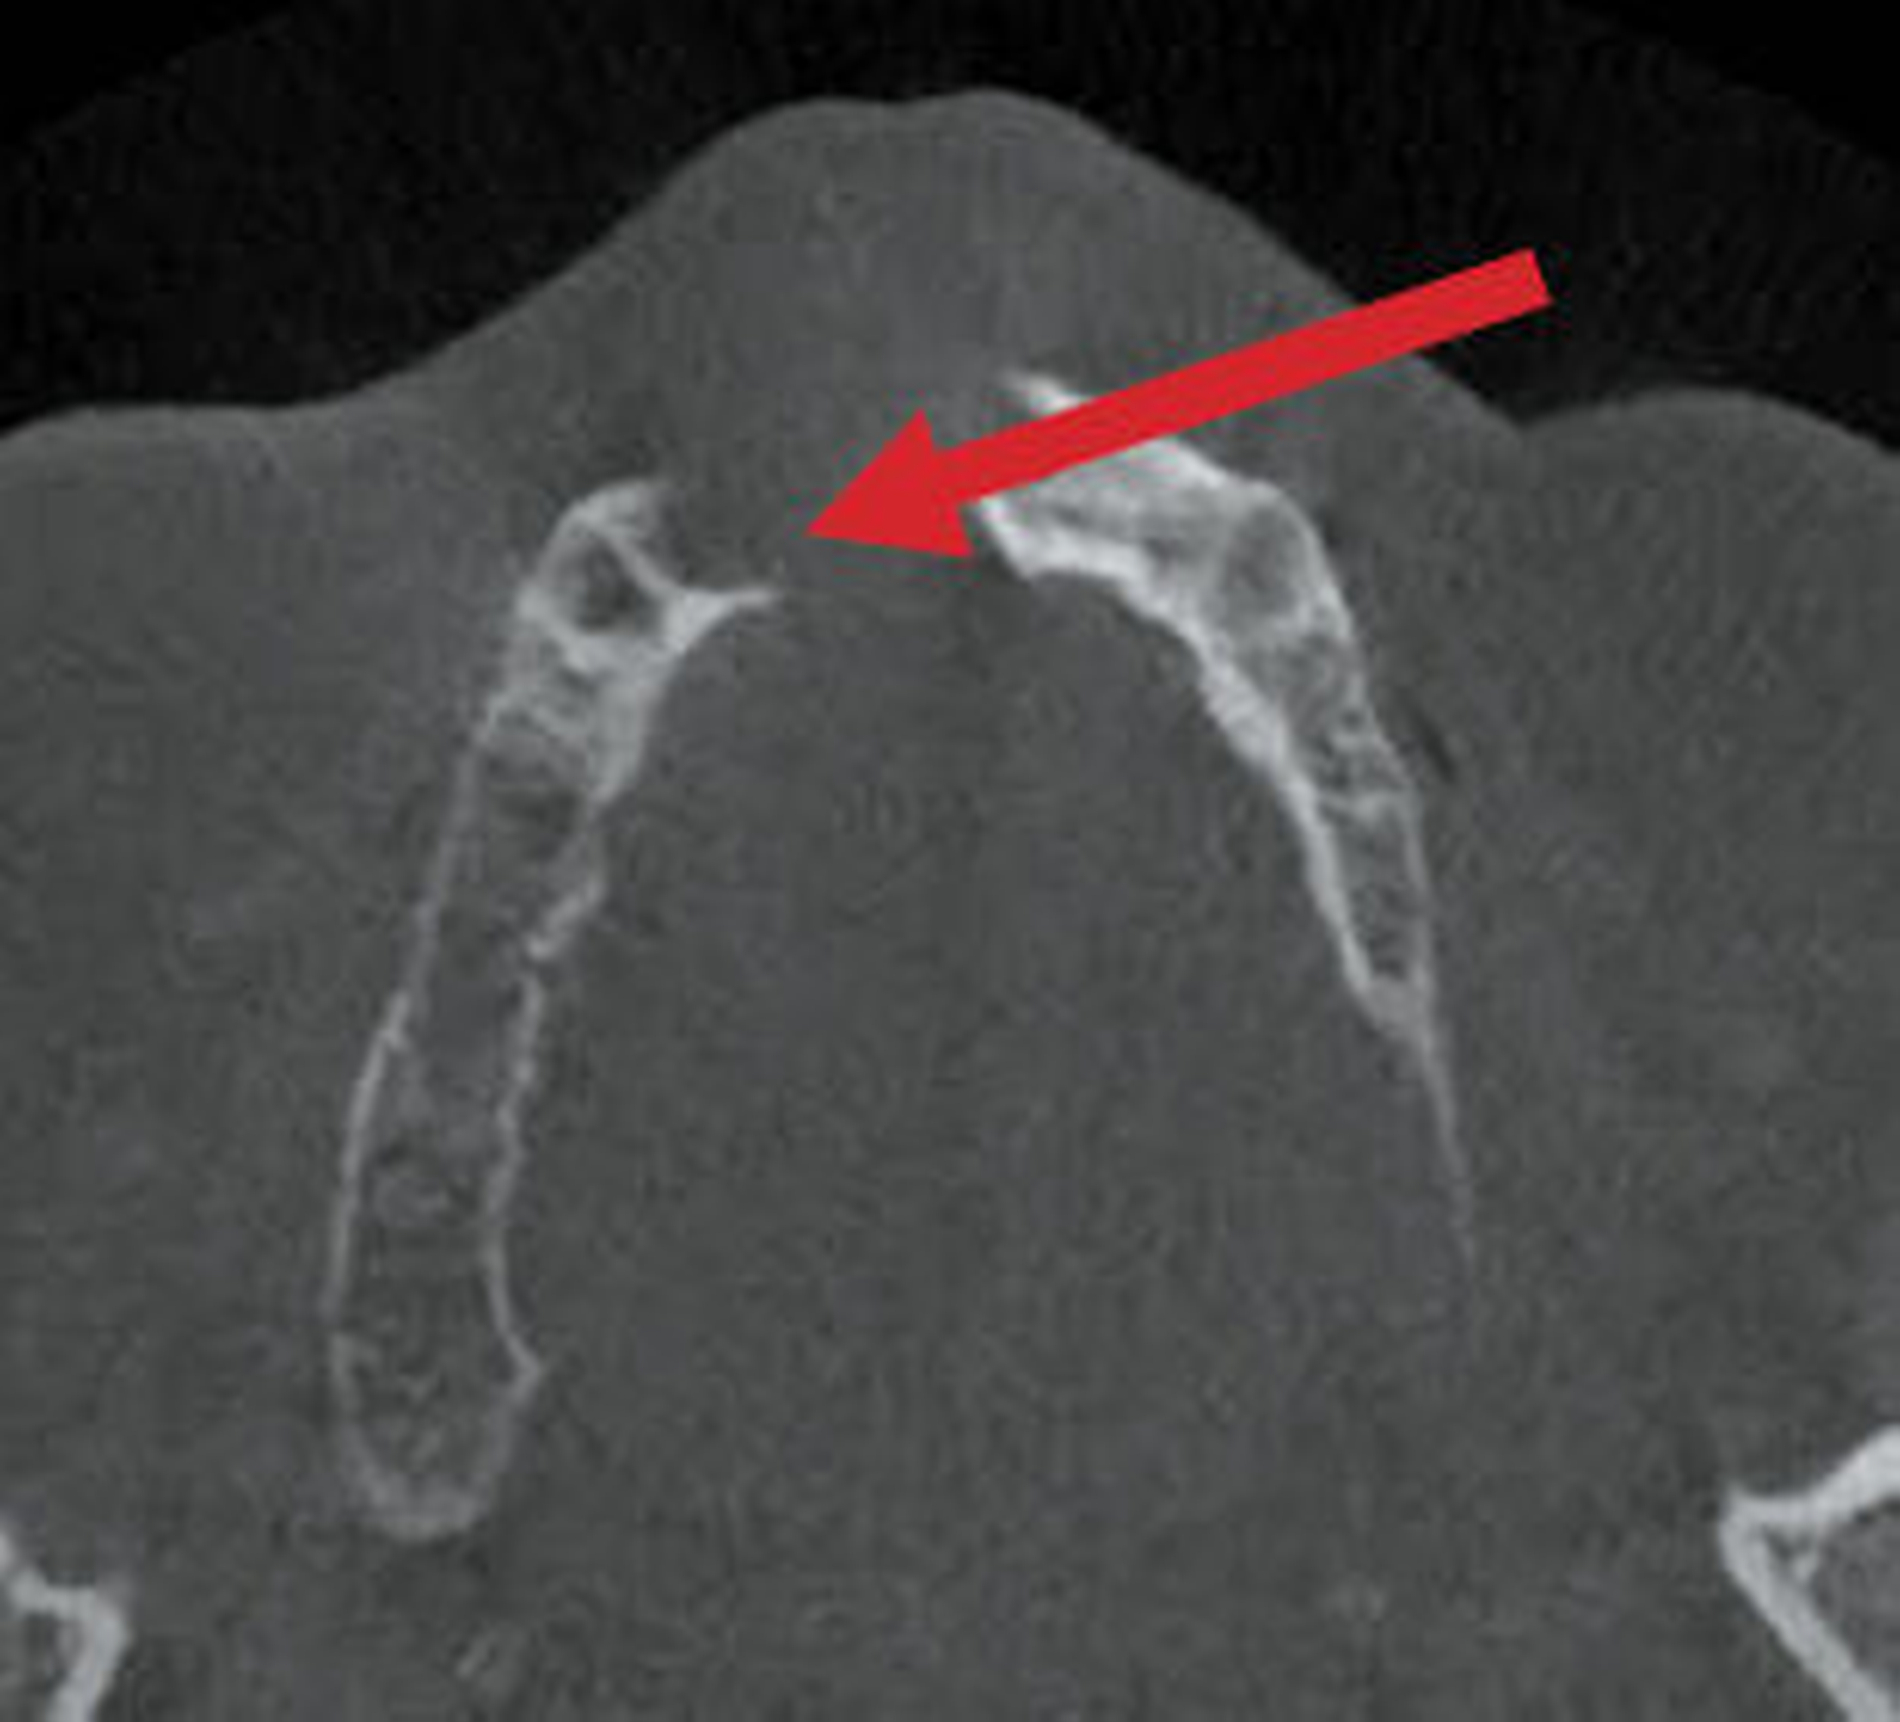

Im DVT sind in allen Raumebenen deutliche Knochendefekte zu erkennen, die zur Unterbrechung des Alveolarfortsatzes in der OK-Frontzahnregion führen. Zusätzlich grenzt sich ein breiter Canalis incisivus ab (Abbildungen 2 bis 4). Ein Rückschluss auf Pathologien im bezeichneten Bereich lässt sich aus den vorliegenden radiologischen Unterlagen nicht ziehen.